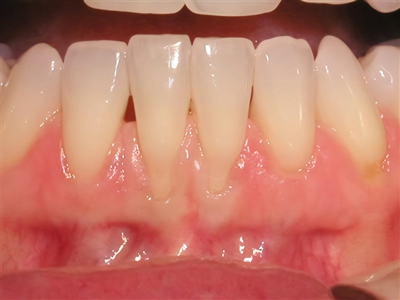

牙龈退缩多颗牙露出黄色牙根图

牙龈退缩导致上牙和下牙的牙根处组织萎缩,牙根处出现月牙状的沟痕,黄色牙根有暴露,患者牙齿敏感,进食冷、酸等食物造成刺激会引起牙齿疼痛。